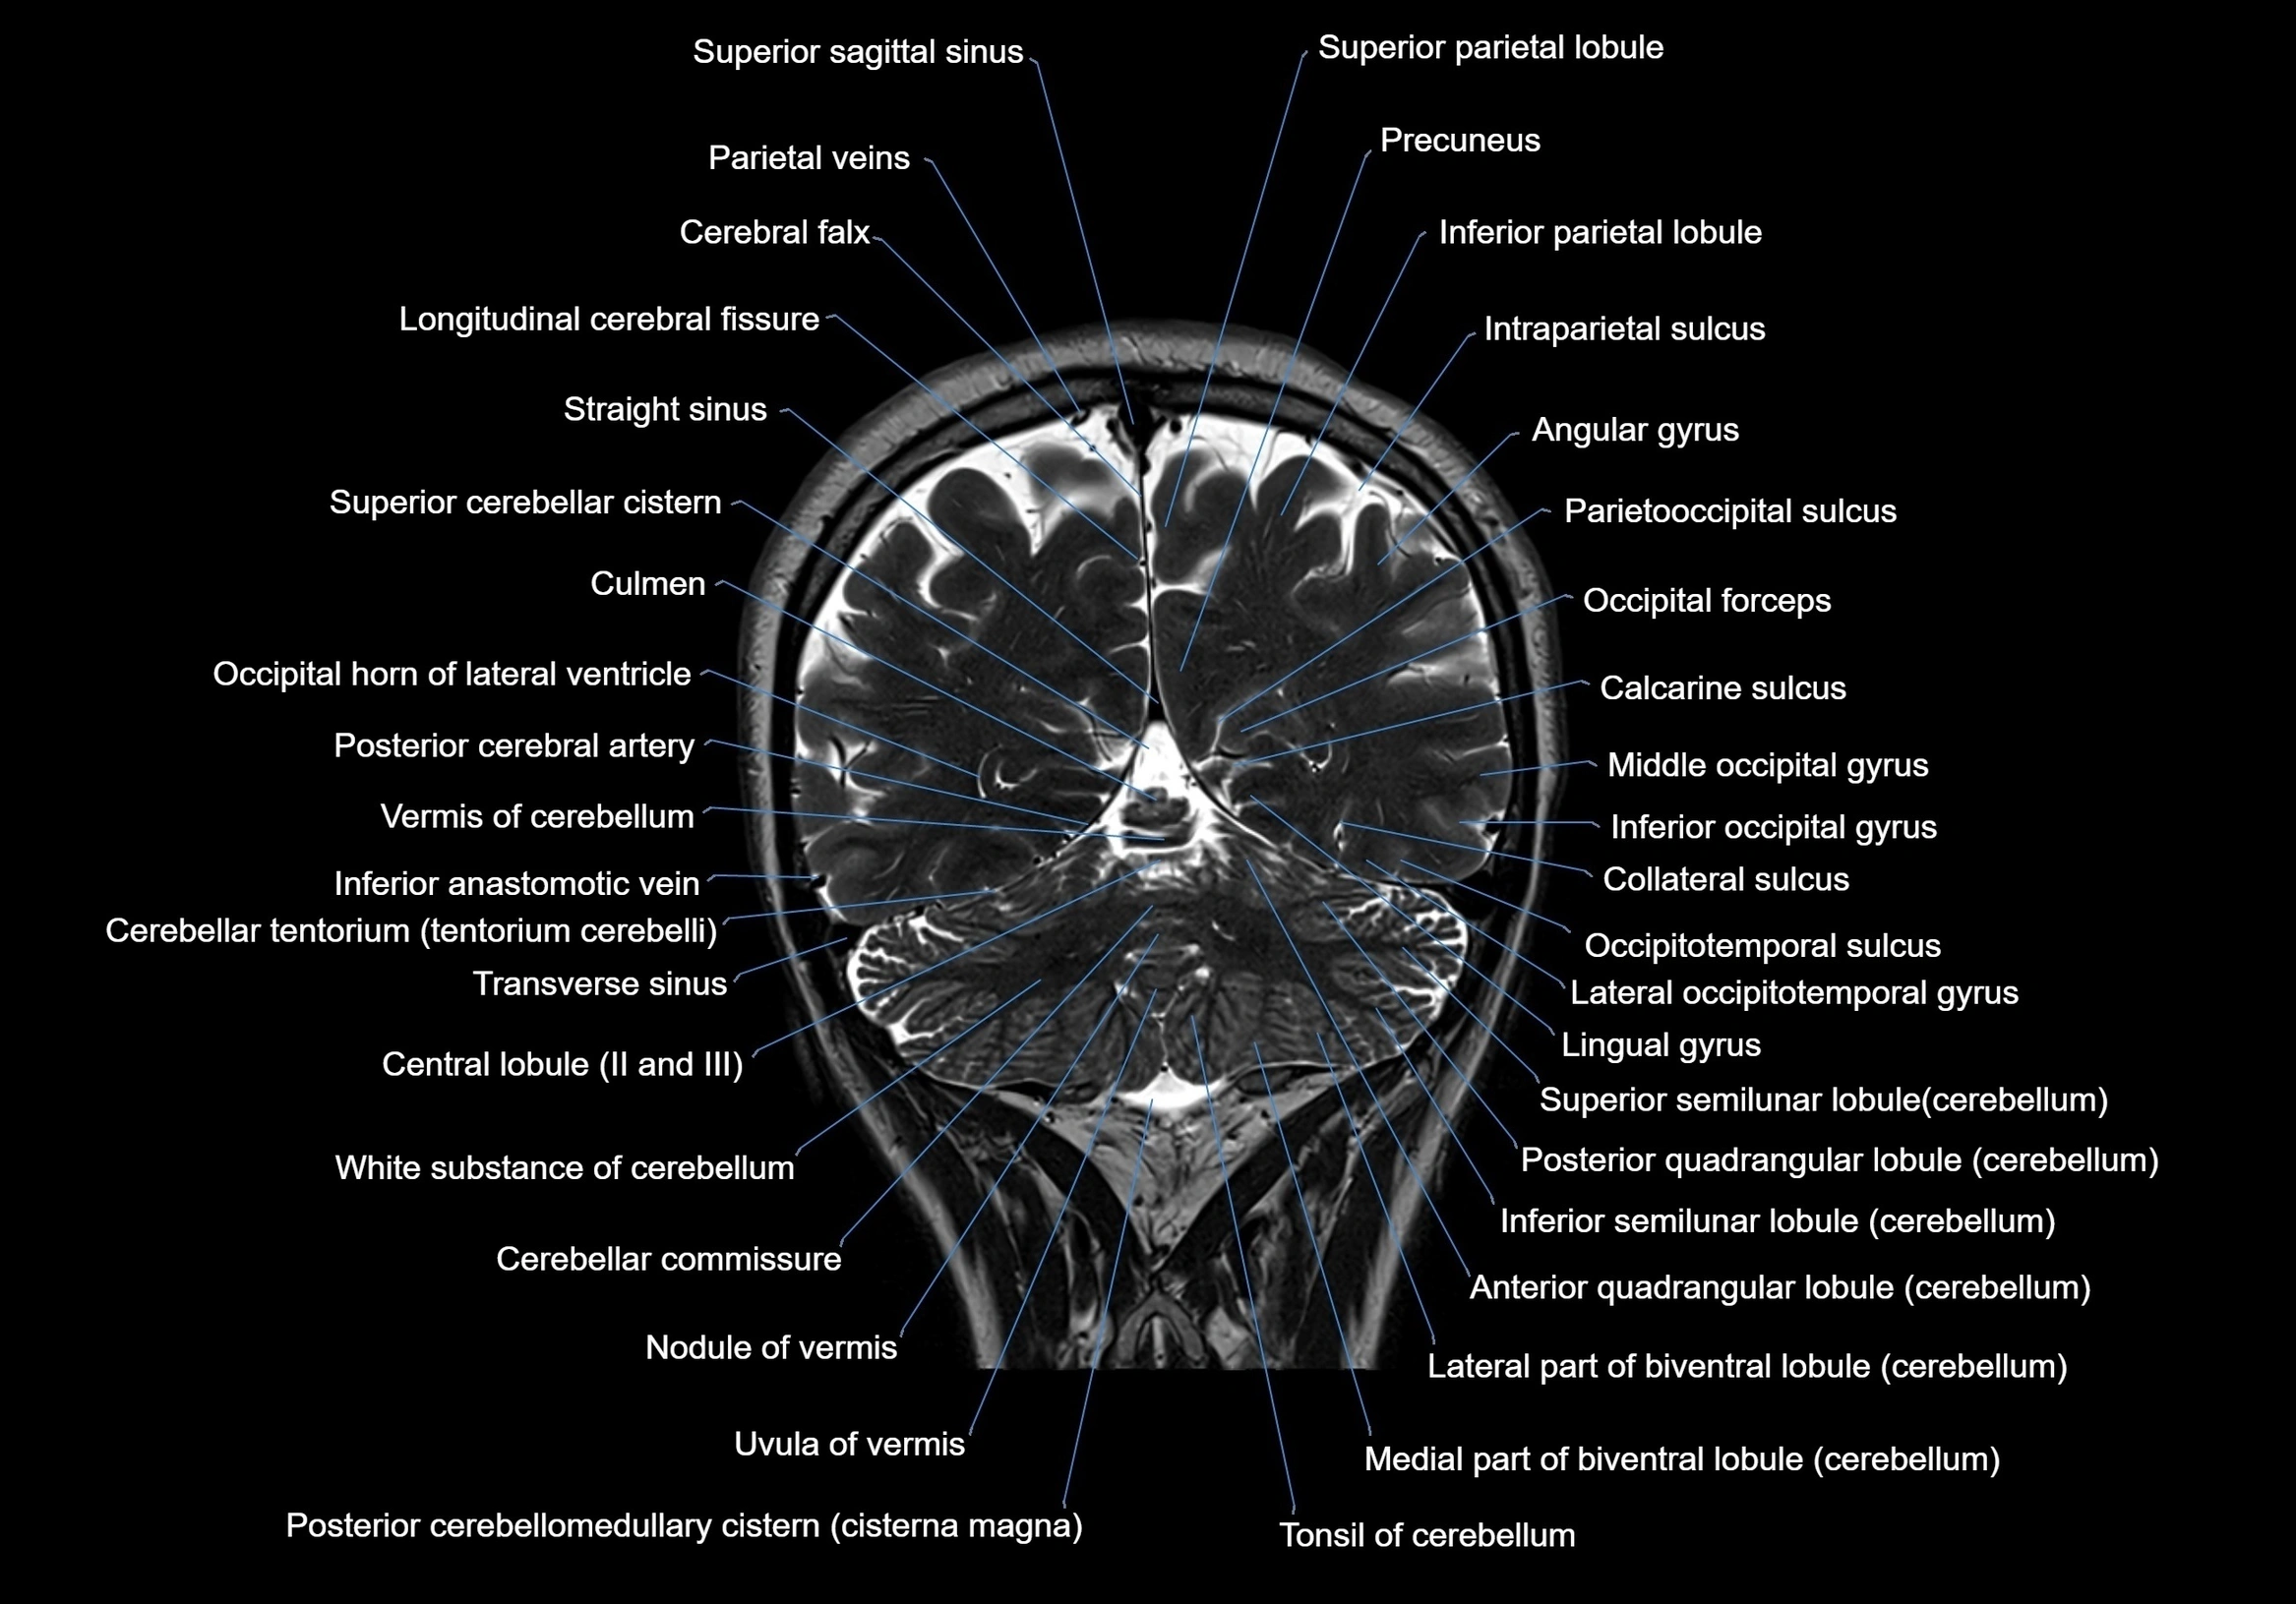

MRI images